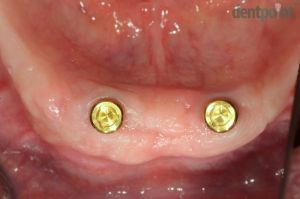

Kivehető implantációs fogpótlás

Implantátumokra rögzített, kivehető fogsor. Páciensünk arcprofilja javult, a rögzített fogsoroknak köszönhetően az ételek megrágása újból akadálytalan és hatékony!

Implantáció: Dr. Molnár Bálint

Fogpótlás: Dr. Molnár Péter

1) Kiindulási helyzet

2) Gyógyult implantátumok

3) Elkészült kivehető fogpótlás

4) Elégedett mosoly